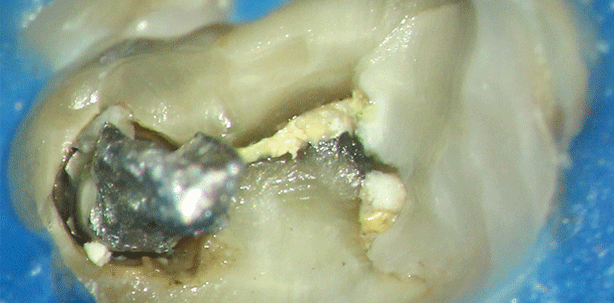

Nach der Darstellung der behandelten Kanaleingänge (Abb. 9) und Entfernung der noch vorhandenen Dentinüberstände mittels Rosen-, Müller- und Munce-Bohrern zeigte sich im Bereich der vermutlichen Lage des zweiten mesiobukkalen Kanals (MB2) ein entsprechender Eingang (Abb. 10). Es wurde mit dünnen Handinstrumenten aus Stahl (Größen ISO 6–10 Taper .02) unter Spülung mit erwärmten Natriumhypochlorit 3 % (NaOCl) ein Gleitpfad angelegt und mit einen Profile 15/.02 der Eingangsbereich langsam rotierend erweitert (Abb. 11). Nach grober Entfernung des alten Füllmaterials mittels Profile 25/.04 in den anderen Kanalsystemen und Erweiterung der Kanaleingänge mit Gates-Bohrern und Ultraschallfeilen (Abb. 12) spürte man im distalen Kanal wie erwartet ein frakturiertes Instrument (Abb. 13). In der mesialen Wurzel liefen MB1 und MB2 im apikalen Abschnitt zusammen. Nach Abschluss der Erweiterung mit Gates-Bohrern der Größe 3 stellte sich in der mesialen Wurzel zwischen den beiden Kanaleingängen nur noch eine schmale Dentinbrücke dar, welcher per Ultraschall entfernt wurde (Abb. 13). Im distalen Kanal wurde das Fragment zunächst mit einem platt geschliffenen Gates-Bohrer der Größe 2 besser dargestellt. Anschließend wurde mit Ultraschallfeilen zunächst distal, nachdem das aber immer mehr in die falsche Richtung führte, dann mesial neben dem Fragment Dentin entfernt. Das Fragment war sehr fest im Dentin verkeilt. (Abb. 14–17). Nach Entfernung sah man in der Tiefe eine Aufteilung des Kanals nach distal und mesial (Abb. 18). Der distale Anteil war bei der Freilegung des Instruments entstanden.